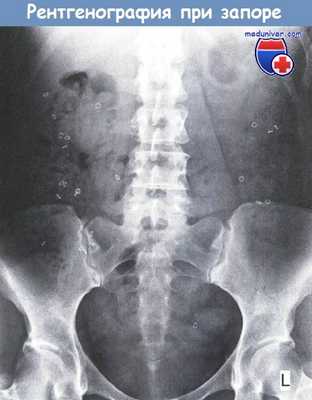

- Исследование транзита по толстой кишке: полная эвакуация радиоконтрастных меток указывает на запор с нормальным транзитом и согласуется с СРК с запорами.

Исследование с рентгеноконтрастными метками при медленнотранзитном запоре (инертная толстая кишка).